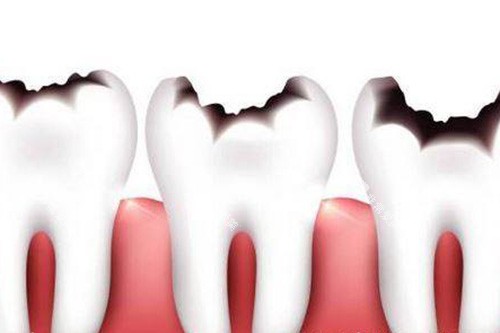

(一)龋齿治疗

龋齿是常见的牙齿问题之一,如果不及时治疗,可能会导致牙髓炎等更重的的问题。